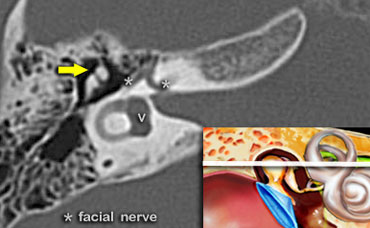

The head of the malleus (yellow arrow) is seen anterior to the head and the short process of the incus.

Geniculate ganglion of the facial nerve

At this level the aditus ad antrum is seen. This is the connection between the tympanic cavity and the antrum.

The labyrinthine segment of the facial nerve coming from the internal auditory canal angles sharply forward, nearly at right angles to the long axis of the petrous bone, to reach the geniculate ganglion.

At the ganglion the facial nerve makes a U-turn (first genu of the facial nerve) to run posteriorly as the tympanic segment along the medial wall of the epitympanum.

Antrum

At this level the antrum is seen surrounded by smaller mastoid aircells just lateral to the superior semicircular canals .